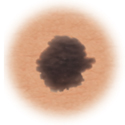

Moles (nevi)

Small skin marks caused by pigment-producing cells in the skin. Moles can be flat or raised, smooth or rough, and some contain hair. Most moles are dark brown or black, but some are skin-colored or yellowish. Moles can change over time and often respond to hormonal changes.

Most moles are benign and no treatment is needed. Some benign moles may develop into skin cancer (melanoma). See below for signs.

Certain moles are at higher risk of changing into malignant melanoma, a form of skin cancer. Large moles that are present at birth and atypical moles have a bigger chance of becoming cancerous. Finding cancerous skin growths early is important. That's when treatment is most likely to be effective. Removing the melanoma through surgery seems to work best. When a melanoma is diagnosed early, surgery usually removes all the cancer.

This is a normal mole.